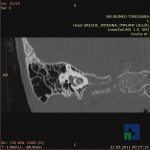

Examinare de rutină cerebrală, nativ și cu substanță de contrast (SDC) pentru diagnosticul:

- Diagnosticul traumatismelor de bază de craniu

- Diagnosticul fracturilor: